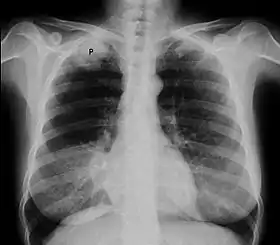

![]() صورة بالأشعة السينية على الصدر يبين ورم بانكوست ( موضح بحرف P ، سرطان الرئة ذو الخلايا غير الصغيرة، الرئة اليمنى) لرئة امرأة مدخنة تبلغ من العمر 47 عاماً. صورة بالأشعة السينية على الصدر يبين ورم بانكوست ( موضح بحرف P ، سرطان الرئة ذو الخلايا غير الصغيرة، الرئة اليمنى) لرئة امرأة مدخنة تبلغ من العمر 47 عاماً. | |